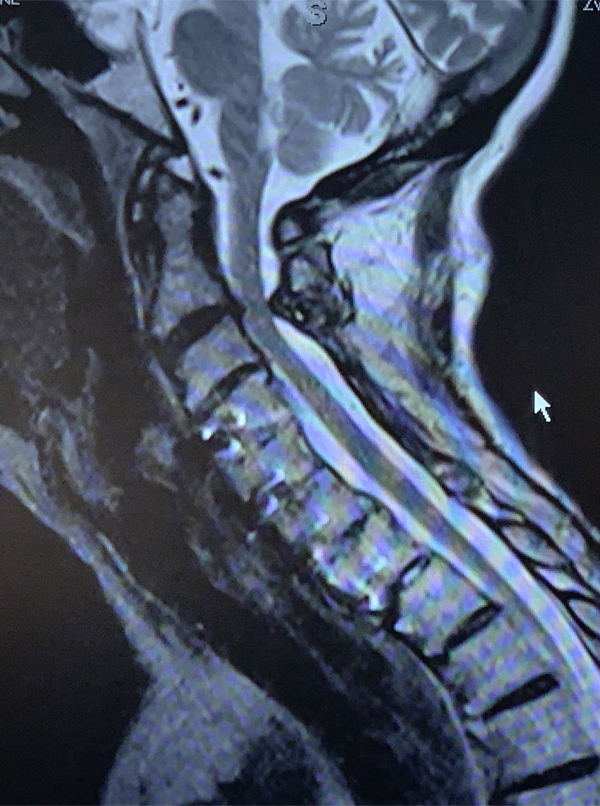

An MRI (Fig. 1) demonstrated severe stenosis at C2-3 with cord compression secondary to significant thickened posterior ligament and facet arthropathy. The patient had a posterior cervical laminectomy C1-3 to decompress the spinal cord and instrumented fusion C2-4.On exploration, the patient was deemed to be fused and the previous hardware was removed except for the lateral mass screws at C3 and C4 were left in. Postoperatively the patient had an uneventful course with some improvement in finger extensor strength.

Figure 1: Sagittal T2 MRI of the cervical spine demonstrates severe spinal cord compression at C2-3 above prior to instrumented decompression and fusion.